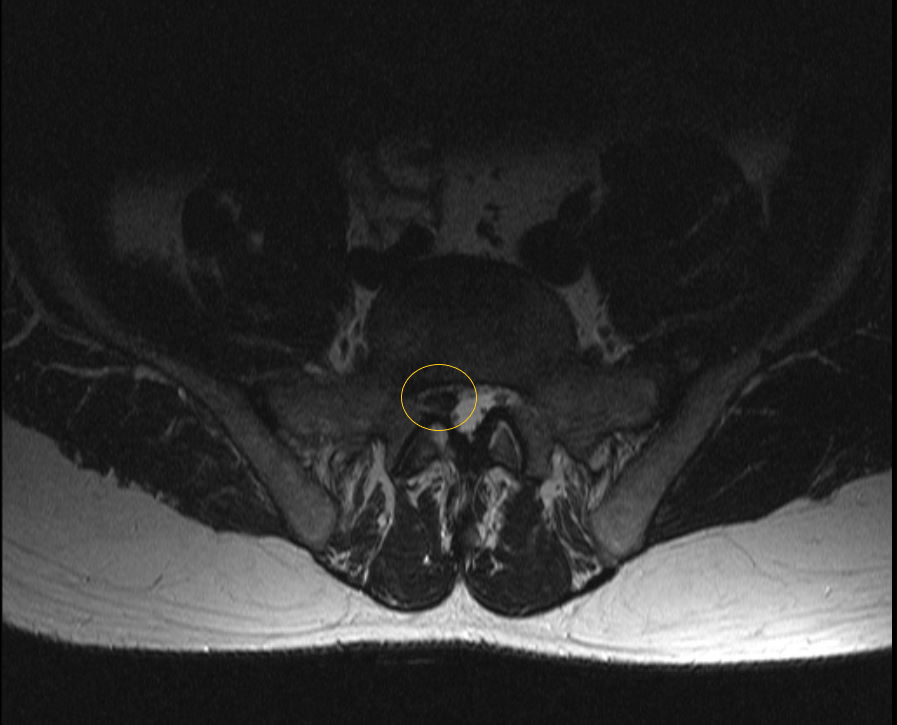

МРТ пояснично-крестцового отдела позвоночника: секвестрированная грыжа межпозвонкового диска между 5 поясничным и 1 крестцовым позвонками без сдавления нервных корешков, положение грыжи срединное.  В такой ситуации операции можно избежать. (данные собственного архива).